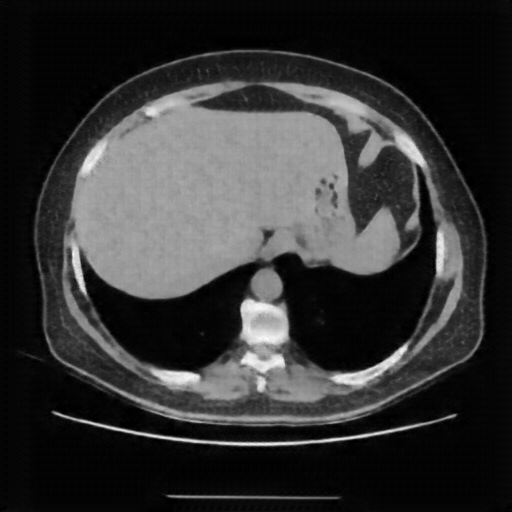

Reconstructed NATIVE CT scan (cycle consistency)

Full window (WL 1023.5, WW 4095 β†’ Low βˆ’1024, High +3071)

Actual HU range: [-1024.0, 609.5]